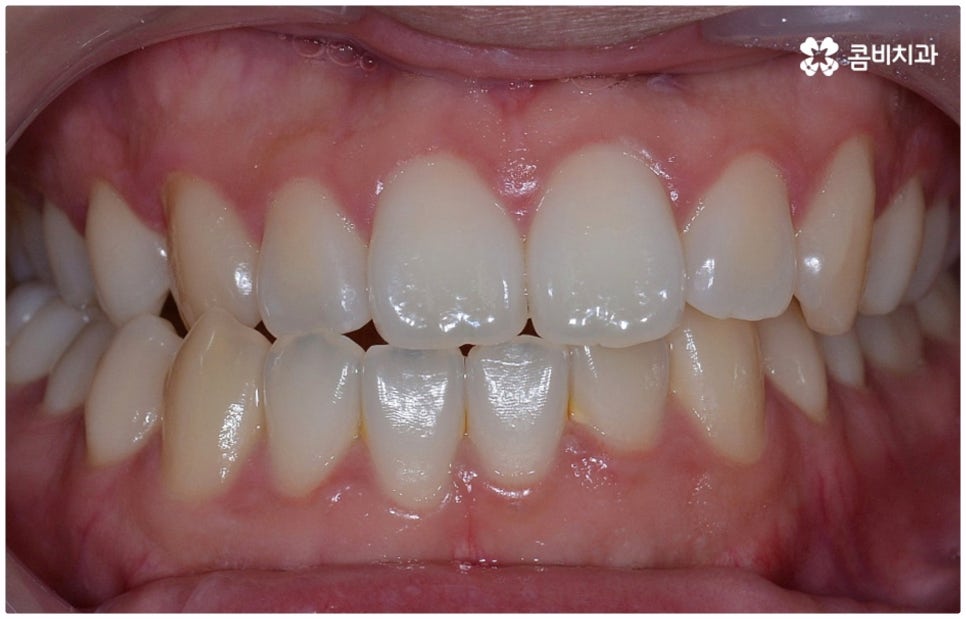

부정교합 3급 이란 입을 다물었을 때 아래 어금니가 윗 어금니보다 전방에 위치한 경우를 가리키는 것으로 그 중 절단교합은 이 상태에서 위아래 앞니 끝과 끝이 맞닿는 교합을 의미하는 거예요. 이에 비해 정상적인 교합은 어금니는 똑바로 맞물리고 윗 앞니는 아랫 앞니를 살짝 덮는 정도로 겹쳐지면서 자연스럽게 조금 앞으로 나와 있는 상태를 말하고 있습니다.

그러나 현재는 이를 바로잡지 않으면 위아래 앞니 사이의 공간이 없기 때문에 어금니가 음식물을 잘게 자르고 부수는 역할을 할 때 생기는 교합력이 앞니에 그대로 전해져서 큰 부담을 주게 되고, 앞니 끝이 부딪히면서 마모가 되거나 치아 수명을 짧아지게 만드는 원인으로 작용하게 될 수 있습니다. 저작 기능을 할 때마다, 즉 식사를 하면서 음식물을 씹을 때마다 치아와 잇몸에 무리한 힘을 가하여 약해지게 만들고 치근까지 좋지 않은 영향을 받게 되는 상황이 발생하므로 교정 치료를 통해 하루 빨리 개선해 주시는 게 좋을 거예요. 특히 절단교합 케이스에서 과도한 교합력이 걸리는 앞니는 심미적으로나 기능적으로나 굉장히 중요한 치아이기 때문에 더욱 주의하실 필요가 있어요.

물론 교정 치료에 적기가 정해져 있는 것은 아니기 때문에 성인 이후 중장년 환자분들이라도 교정 치료가 불가능하지는 않으며 상황에 따라 비수술적인 방법으로도 얼마든지 불편함을 줄일 수 있는 경우가 있으니 정확하게 진단한 후 각자에게 맞는 교정 계획을 세워 무리하지 않게 치료를 진행하시길 바라고 있어요. 특히 턱관절과 관련된 부분을 개선하기 위해서는 양악 수술 밖에 방법이 없는 것이 아닌가 생각하셨던 분들이라면 먼저 치과에 내원하셔서 검진과 상담부터 진행해 보시면 마음의 부담을 덜 수 있어 좋을 거예요. 부정교합 3급 치열 (절단교합과 일부 반대교합이 병행되어 있음) 을 가지고 있는 성인분도 교정 치료를 통해 훨씬 자연스럽게 개선이 가능할 수 있으며, 관련 기술 개발 및 미니스크류 등 여러 장치의 발전을 통해 예전에는 적용이 어려웠던 케이스들도 이제는 교정 치료의 도움을 받을 수 있습니다.

전체 치료 기간은 약 18개월이 소요되었으며,